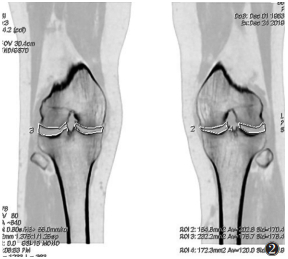

1.4 图像分析将重建的1.25 mm单能量图像上传至AW4.6工作站并采用GSI General MD分析软件行常规CT三维重建和基物质分离后处理,重建得到脂肪/肌肉和骨/脂肪基物质对图像、常规CT图像。由2位高年资骨肌系统影像科医师对能谱CT图像进行评价:在矢状位髌下脂肪垫(infrapatellar fat pad,IPFP)最大层面勾画边界,获得脂肪(肌肉)基物质图像及其脂基物质含量和常规CT图像及其平均值(图 1),根据胫股内侧区(股骨内髁与胫骨髁间隆突内侧的胫骨平台形成的关节区域)和胫股外侧区(股骨外髁与胫骨髁间隆突外侧的胫骨平台形成的关节区域)分区,在骨(脂肪)基物质图像获得冠状位内外关节间隙最大面积(图 2),并依据K-L评分对骨赘进行分级;以上数据取2位医师测量的平均值,主观分级由2位医师商议后确定。

![]() |

| 注:骨(脂肪)基物质图像获得冠状位内外关节间隙最大面积,左侧膝关节胫股内侧区面积为154.6 mm2,胫股外侧区172.3 mm2 图 2 骨(脂肪)基物质图像获得冠状位内外关节间隙最大面积示意图 |